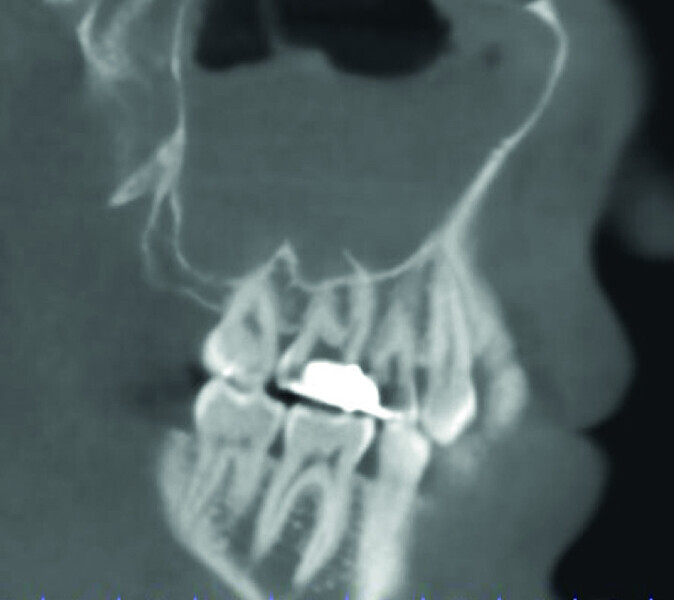

Maxillary sinus and root canal therapy complications